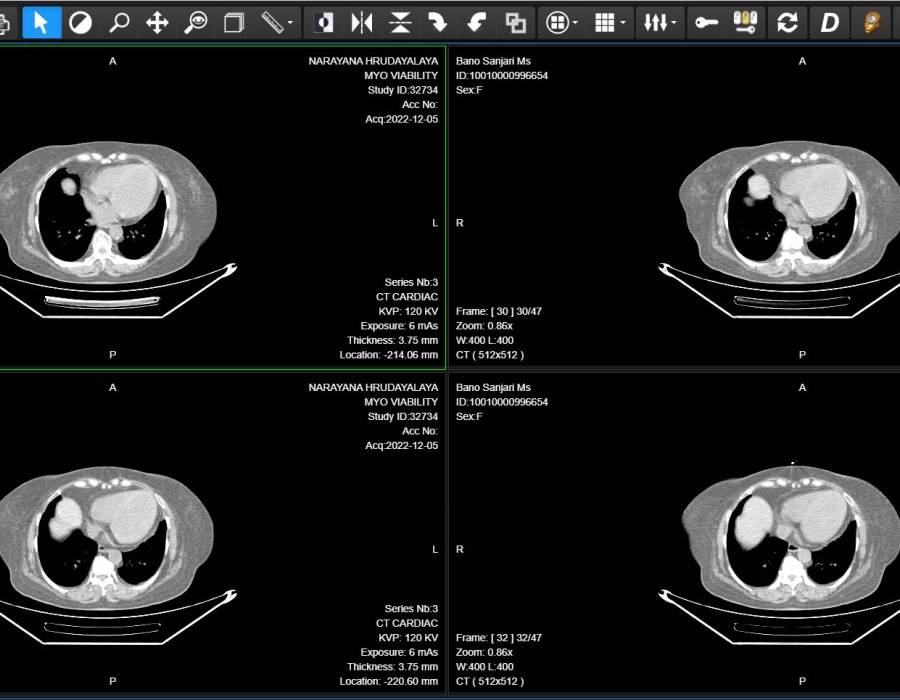

A CT scan viewer is a software tool designed to display and analyze images generated by a CT scanner. CT scans provide detailed cross-sectional images of the body, allowing physicians to view tissues, organs, and bones in three-dimensional space. These scans are crucial for diagnosing a wide range of conditions, including cancer, cardiovascular disease, fractures, and neurological disorders. The CT scan viewer is responsible for rendering these images, allowing healthcare professionals to zoom, rotate, and manipulate the images for better clarity.

A key feature of CT scans is their ability to capture cross-sectional images of the body. These slices provide doctors with detailed views of individual organs, tissues, and bones, which can be used for comprehensive analysis. CT scan viewers enable healthcare providers to scroll through these slices and examine them layer by layer, offering a clear and accurate representation of the patient's anatomy. This cross-sectional approach helps doctors gain a deeper understanding of the patient's condition, leading to more accurate diagnoses and treatment plans.